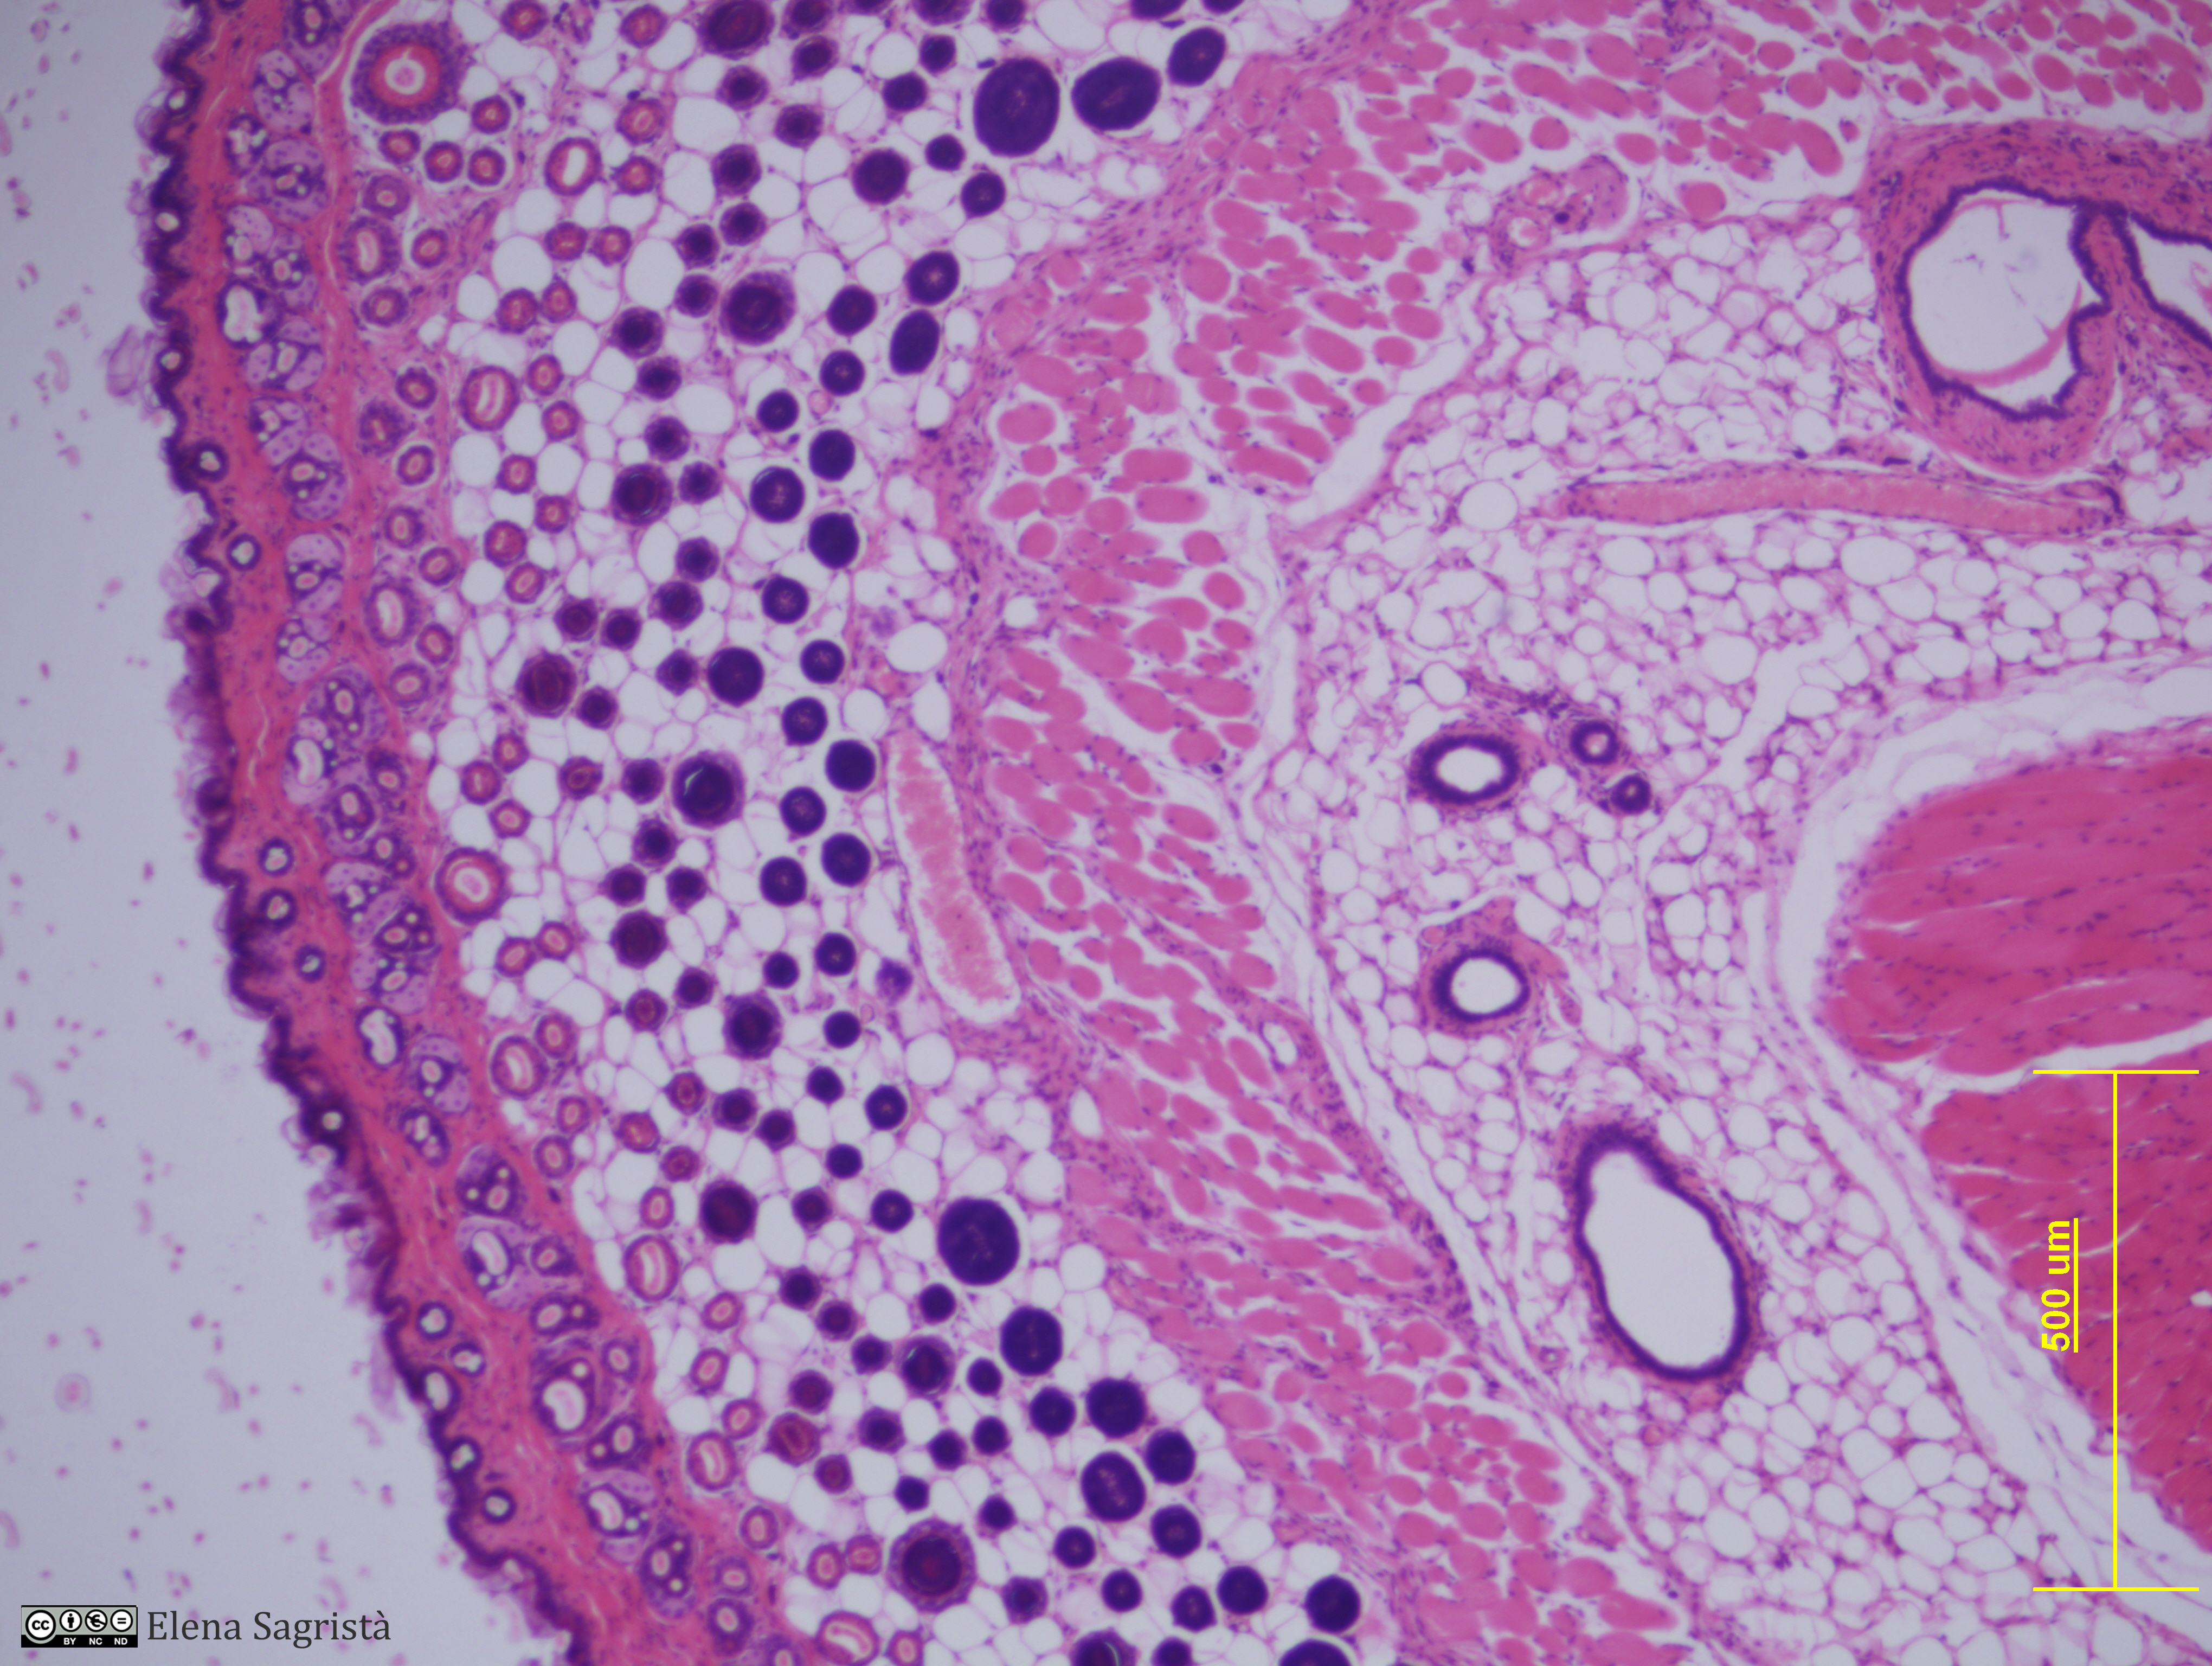

Histologia imatges: 11 Pell

Imatges de preparacions histològiques de Pell. Microscopia òptica.